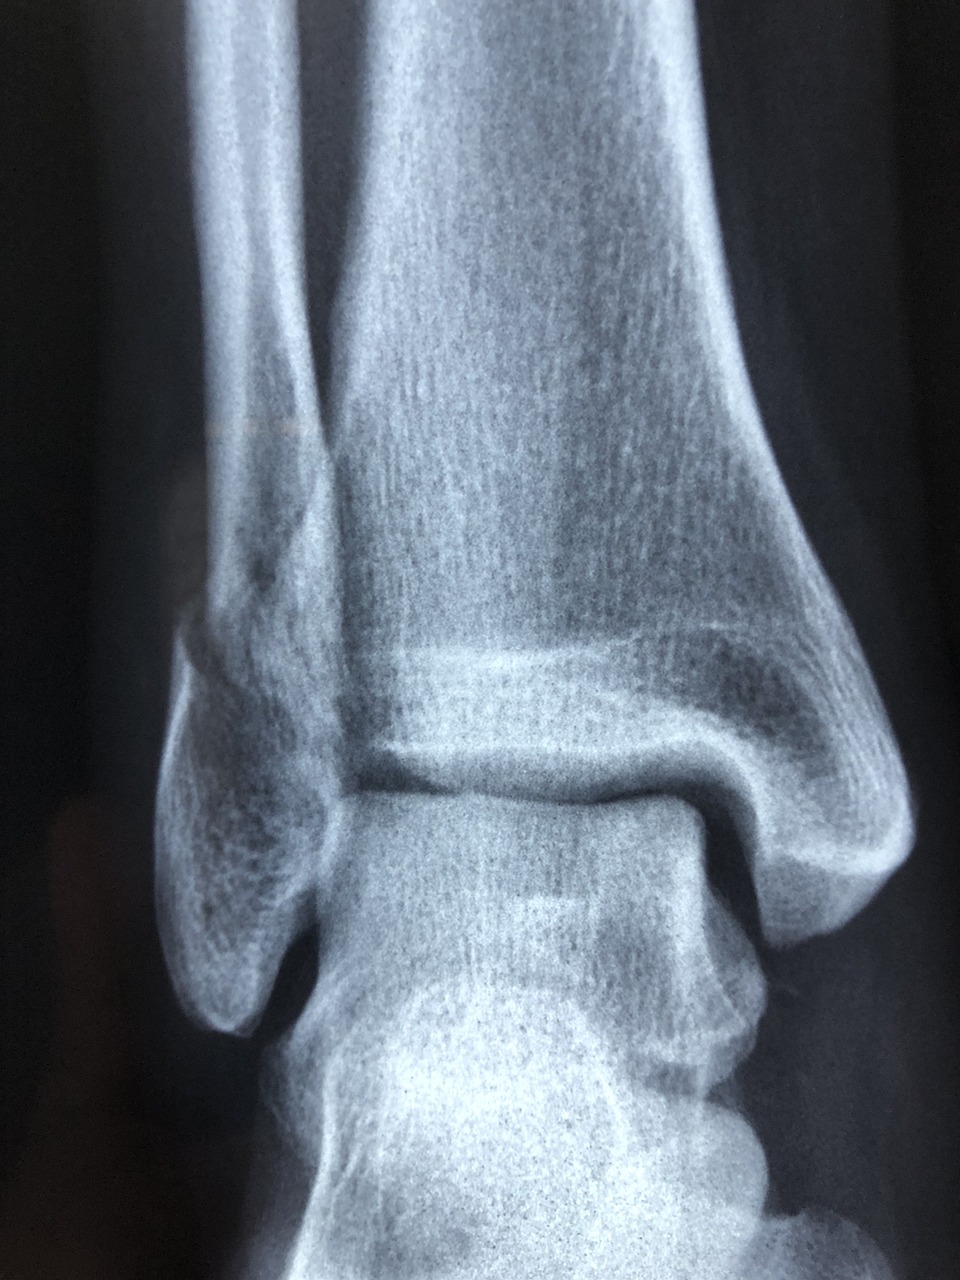

足関節(足首)は、脛骨・腓骨・距骨の3つの骨で構成されています。この関節を安定させているのが「靭帯」です。足首の外側にある外側靭帯は3つから成り立っています。

症状が重篤な場合は、まず整形外科などの医療機関でレントゲンやMRIによる検査を受けてください。

場合により医療機関で、X線(レントゲン)撮影・MRI・筋電図・血圧測定などの検査を行い、その他の疾患の有無を調べる必要があります。